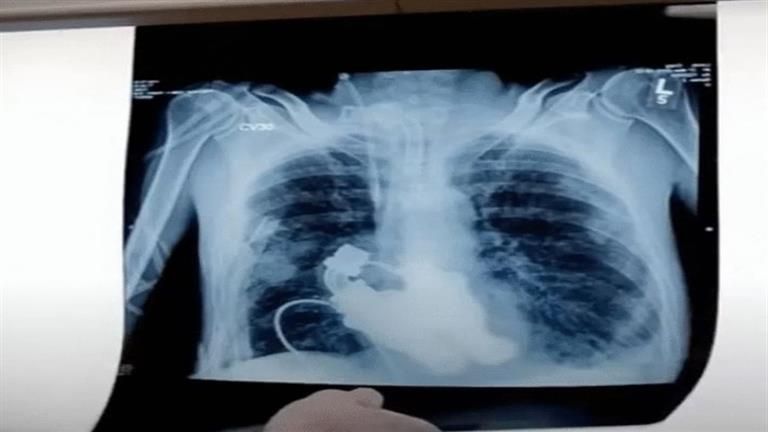

وتمت تجربة القلب التجريبي على الحيوانات، ولكن كريج كان أول إنسان يخضع لهذا الإجراء، و قام الدكتور كوهن والدكتور فرايزر بإزالة قلب كريج وتركيب الآلة ونجا من العملية وبدأ تعافيه، وبعد سعادة زوجته وشعورها بأمل جديد، فاجئهم المرض بمهاجمة الكبد والكلى، وبعد أن عاش لمدة شهر بقلب ميكانيكي، فارق الحياة في إبريل عام 2011.

وقبل استبدال قلب كريج، جرب الأطباء هذه الأداة على 38 عجلا، بما في ذلك عجل يبلغ من العمر ثمانية أشهر يدعى أبيجيل، أزالوا قلبها وأدخلوا مضختين للطرد المركزي ما دفع الدم حول جسم العجل، وفقًا لتقارير LadBible.